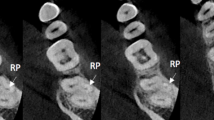

Definition of landmarks

The sections of mandible and fibula of each patient were reviewed to create a three-dimensional model based on DICOM data of CBCT and CTA, respectively. Fibula morphology was evaluated at three cross-sectional segments with landmarks as follows: Side D was set as 80 mm from the distal end of fibula, Side M was the midpoint of fibula, and Side P was 80 mm from the proximal side of fibula (Fig. 1A). In terms of mandibular morphology, the landmarks were set as transverse plane of anterior, premolar and molar areas. The anterior and premolar areas were located at the incisors and the premolars, respectively. The molar area was located at the distal of the second molar (Fig. 1B)8.

Each cross-sectional slide was calculated including the vertical height and transverse widths according to previous studies8,9. The vertical height was determined and measured by a line drawn through the long axis of the fibula or mandibular cross-sectional area, with the longest distance, which was marked as H. The transverse widths measurements were recorded perpendicular to the long axis line at two locations, one of which was drawn at upper one third of vertical height marked as W1, and the other was at lower one third of the vertical height marked as W2 (Fig. 1). The vertical height and transverse widths of the selected sections from each mandible and fibula was measured 3 times by two independent observers (Xiaojie Ma and Zhuo Wang) using Proplan software.

We analyzed the morphology at the planes of Side D, M and P based on 3D reconstruction of fibula and found 3 types including circular, triangular and square according to the classification of a previous study (Fig. 1A)8. Statistically, a total of 87 cases of the cross-section was circular (75.4%), 18 (15.3%) was triangular and 11 (9.3%) was square at Side D. At Side M, triangular was observed in 80 cases (67.8%), square was in 36 cases (30.5%), circular was in 2 cases (1.7%). At Side P, 58 cases (49.2%) were triangular, 48 cases (40.7%) were square and 12 cases (10.1%) were circular (Table 2).

Six cases were excluded since the primary lesions involved nearly total mandible could not be calculated. Besides, 10 cases of anterior area, 2 cases of premolar area and 1 cases of molar area were excluded as these regions were related to primary lesion or performed surgeries before. According to our results of the selected areas, we found 3 types of morphology: straight, oblique, and s-shape (Fig. 1B). In anterior area, the most of the cross-section was s-shape (n = 89, 90.82%), while 8 Sections (8.16%) were straight and 1 (1.02%) was oblique. In premolar area, 92 Sections (83.64%) were straight, 12 Sections (10.91%) were oblique and 6 Sections (5.45%) were s-shape. In molar area, 102 Sections (91.89%) were oblique and 9 Sections (8.11%) were straight (Table 2).